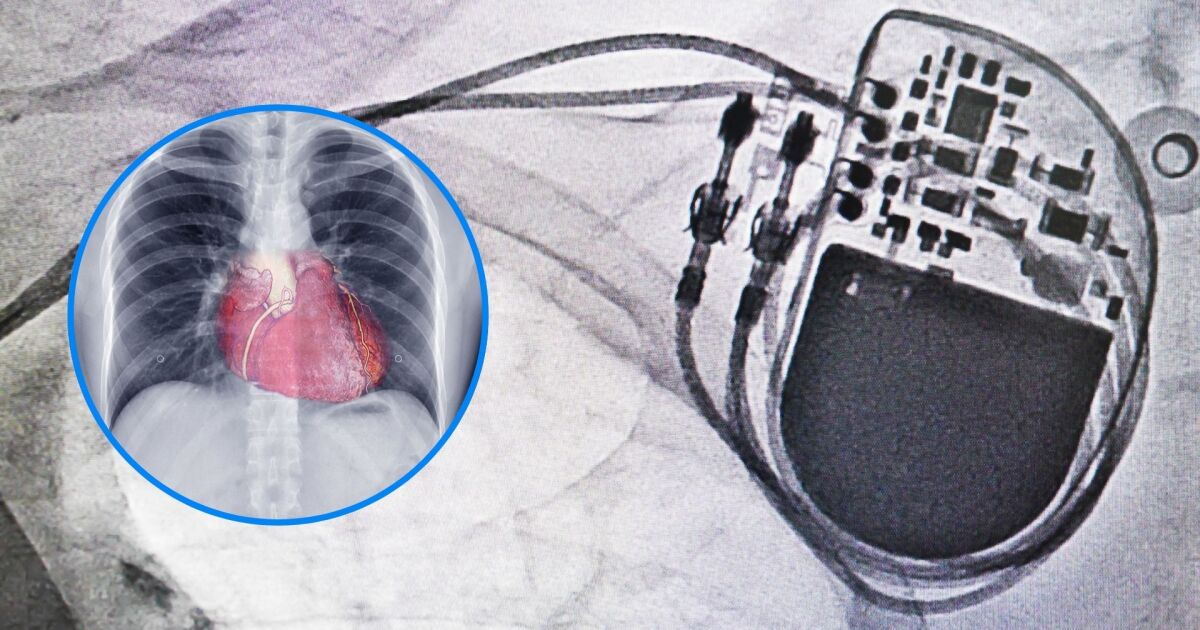

Според експертите от Mayo Clinic, съществуват два типа постоянни пейсмейкъри: трансвенозен и безжичен (leadless). Вашият сърдечен екип ще определи кой тип е най-подходящ за вас въз основа на медицинското ви състояние и начин на живот.

1. Трансвенозен пейсмейкър

Трансвенозният пейсмейкър е класическият вариант, който е използван от десетилетия с отлични резултати. При имплантирането на този тип кардиостимулатор:

- Кардиолог-електрофизиолог създава малък джоб точно под ключицата между кожата и гръдния мускул

- До три електрода (наричани водачи) се въвеждат през кръвоносен съд към сърцето

- Водачите се свързват към пейсмейкъра, който след това се поставя в джоба